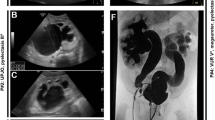

At the age of 14 years the proband was seen in the clinical genetics clinic at the Center for Medical Genetics (GENESIS, Poznan, Poland). At this time, multiple dysmorphic features were clearly noticeable (Fig. 1). Skeletal abnormalities included short stature (height 133 cm, weight 23 kg), scoliosis, contraction of the left forearm and left hand, phalangeal hypoplasia, hypoplastic thumbs, absent radial bones, left clubfoot varus and syndactyly (2nd and 3rd toes). Facial dysmorphic features included macrostomia (repaired surgically at the age of 15 months), narrow palpebral fissures and right auricular tags. Neurological evaluation revealed severe neurodevelopmental delay. A generalized hypotonia was present since birth. The patient had a reported history of epilepsy characterized by involuntary ocular movements for which she was maintained on antiepileptic medications. Brain imaging documented cerebral atrophy with agenesis of corpus callosum (ACC) (Fig. 2). In addition, the patient had a history of mild myopia, but fundoscopic exam revealed no major retinal abnormalities. Her hearing was intact.

The patient also had several malformations of internal organs. Early echocardiographic evaluation revealed patent ductus arteriosus with aortic coarctation (repaired surgically at the age of 7 weeks), a small ventricular septal defect, a patent foramen ovale and an asymmetric bicuspid aortic valve. The urogenital abnormalities included complete right renal agenesis, grade IV left VUR, left-sided hydronephrosis and a prominent clitoris. A successful surgical anti-reflux procedure was performed at the age of 2 years, with follow-up voiding cystourethrogram showing only mild (grade I) residual left-sided VUR. The parameters of renal function (blood urea nitrogen and creatinine) remained within normal limits for her age, and there was no evidence of proteinuria on serial urinalyses after the procedure. Additionally the patient had left thyroid lobe hypoplasia and associated hypothyroidism. This diagnosis was established at the age of 16 months: thyroid-stimulating hormone (TSH) level was 4.2 mU/l (normal 0.4–4.0 mU/l), FT4 level was 8.1 pmol/l (normal 8.5–19.0 pmol/l), and thyroid ultrasound revealed a small hypoechoic thyroid gland with severe left lobe hypoplasia. At this time, the patient was initiated on thyroid hormone replacement therapy.